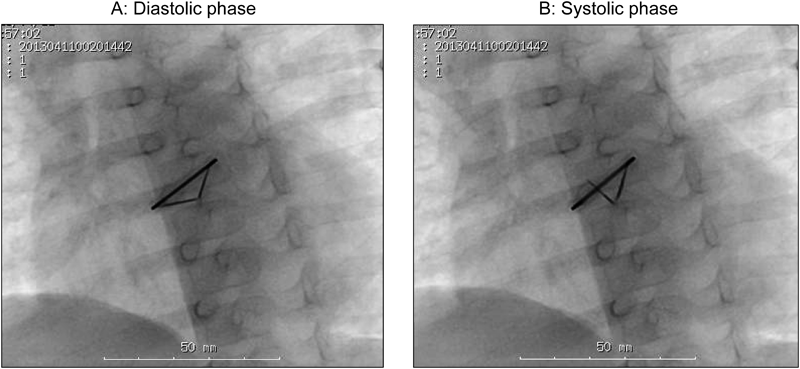

体格の小さい幼小児に対して機械弁置換を施行する場合,その後の成長により弁輪径は必然的に相対的狭小化をきたすため,手術時には可能な限り大きい径の機械弁を挿入することが想定される.先天性心疾患で,小児期に大動脈弁位への機械弁置換の対象となる疾患としては,重症大動脈弁狭窄症に加えて総動脈幹症が考えられるが,総動脈幹症では,大動脈弁として機能する弁輪の径が,正常の大動脈弁輪径より大きい.これは先述の成長の要素を考えるときには有利に思われる点であるが,機械弁では体格に対する弁輪径が大きいほど通過血流速度が遅くなり,血栓弁もしくは血栓症の頻度は高くなることが指摘されている35, 36).かつ,総動脈幹症では大動脈弁位が両心室にまたがる形態となり,左心室からの血流の方向が複雑で,それにより弁葉の開きが悪くなる可能性があり,これも血栓弁のリスクを増加させる一因となり得る.したがって総動脈幹症に対して大動脈弁位に機械弁を挿入した小児においては,血栓弁により注意を払う必要があると考えられる(Fig. 1).

Pediatric Cardiology and Cardiac Surgery 32(1): 9-18 (2016)

Fig. 1 Findings of the fluoroscopy

The fluoroscopy revealed a stuck prosthetic aortic valve with one leaflet completely immobile.

1歳3か月,男児.総動脈幹(A2),総動脈幹弁逆流>3/4,総動脈幹弁狭窄=3.5 m/sの診断に対し日齡5に両側肺動脈絞扼術,月齡6に心内修復術(大動脈弁置換;SJM#17,Rastelli手術)を施行された.月齡9に人工弁不全(一葉閉鎖位固定,一葉半開放)を来し血栓溶解療法を行ったが効果不十分で,血栓及びパンヌス除去術を施行された.以後WarfarinとAspirinを併用し,PT-INR 2.5–3.0で管理していた.

入院の10日前に3回の嘔吐が出現したが神経学的異常所見なく,Domperidone投与で速やかに改善した.入院前日の朝から活気低下,夜間に38.5°Cの発熱を呈し,嘔吐,機嫌不良も出現した.頭部CT検査(Fig. 2(A))で左大脳半球表面に広範な硬膜下血腫を認めた.体表面に明らかな痣や外傷はなく,栄養状態は良好,皮膚の清潔も保たれ虐待は否定された.同時に機械弁開放/閉鎖音の減弱を認め,人工弁透視検査(Fig. 1)を施行したところ一葉が閉鎖位で固定していた.心臓超音波検査では,大動脈弁通過血流速度2.8 m/sと,発症前の2.1~2.5 m/sより若干加速していたが,心機能は良好で心不全も来していなかった.PT-INRは5.08と顕著に延長していたため,FFP(90 mL:10 mL/kg),Vitamin K2(4 mg)を投与しPT-INRは8時間後に2.01に低下,さらにFFP(90 mL:10 mL/kg)を追加し24時間後に1.25まで低下した.入院2日目の頭部CTでは血腫の増大は見られなかった.この間,APTT 70 sec.を目標に未分化Heparinを持続投与した.入院5日目,頭部CTで血腫は吸収,縮小したが左中大脳動脈領域に梗塞像が出現した(Fig. 2(B)).右握力は僅かに低下していたが他の麻痺や痙攣は認めなかった.入院12日目の頭部CT(Fig. 2(C))で血腫はほぼ吸収されていることを確認し,PT-INR2.0を目標にWarfarin内服を再開した(Fig. 3).人工機械弁の一葉完全開放,一葉閉鎖位固定の状況には変化がなかったため待機的再手術の方針とし,ICH発症4か月後に再弁置換術を施行した.ICHの再発は認めず,右握力は発症前と同等に改善し,他の麻痺,痙攣を含む神経学的後遺症も認めていない.